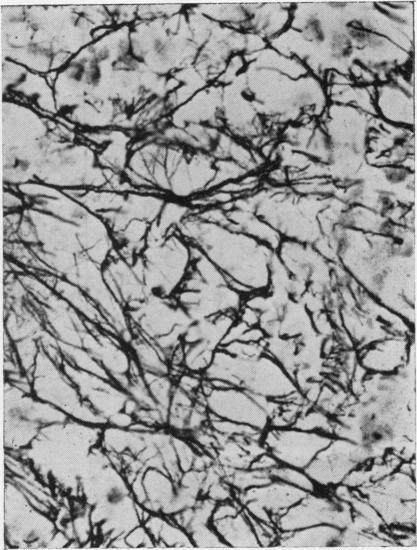

The stromal structure of the bone marrow was studied in 96 cases of leukaemia and related disorders. The reticulin stroma forms an integral component of any given marrow proliferation and may often be increased in amount, sometimes normal, and occasionally decreased. The pattern is often indeterminate but certain distinguishable patterns may be found, including a sinusoidal pattern in myelofibrotic chronic myeloses, a pattern characterized by an abundance of hyperplastic capillaries and arterioles often seen in lymphoid leukaemias, and one with irregular focal reticulin proliferation in many acute undifferentiated leukaemias.Adventitious collagen fibres are demonstrable in about half of all myeloses, acute and chronic, leukaemic and aleukaemic, and may be diffuse or focal. They apparently develop from thickening and collapse and condensation of the basic reticulin network, not from any primary fibroblastic proliferation. The development of fibrosis does not denote an aetiological relationship between the conditions in which it occurs, since it appears to be a non-specific sequel to marrow exhaustion and marrow necrosis. There is no justification for the diagnosis of acute or ;malignant' myelofibrosis as a disease entity in cases of acute leukaemia with marrow fibrosis.Osteolytic change due to resorption of bony trabeculae is a common event in all the conditions studied and may be accompanied by remoulding of the eroded trabeculae. Fibre bone formation is found in about 15% of cases, including acute lymphoblastic leukaemias and acute undifferentiated leukaemias, but is extensive and well-developed only in cases of primary myelofibrosis.